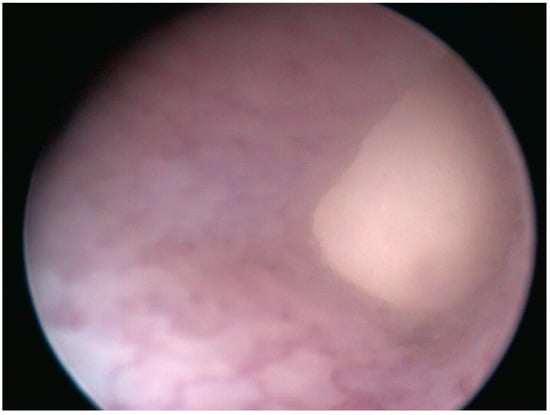

2.2.3. Case 3